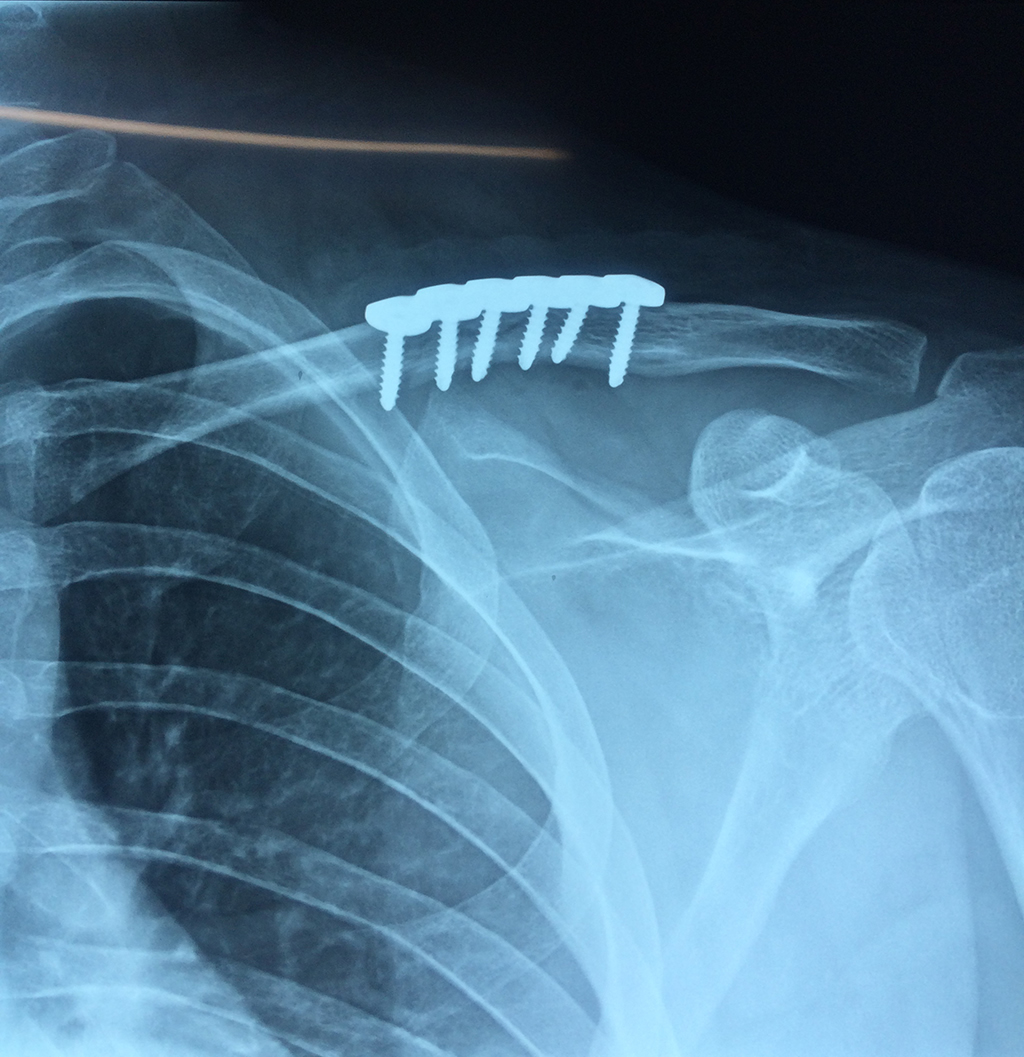

Cirugías

La clavícula es un hueso largo, con forma de "S" itálica, situado en la parte anterosuperior del tórax. Junto con la escápula forman la cintura escapular. Se puede palpar por toda su longitud y se extiende del esternón al acromion de la escápula, siguiendo una dirección oblicua lateral y posterior.